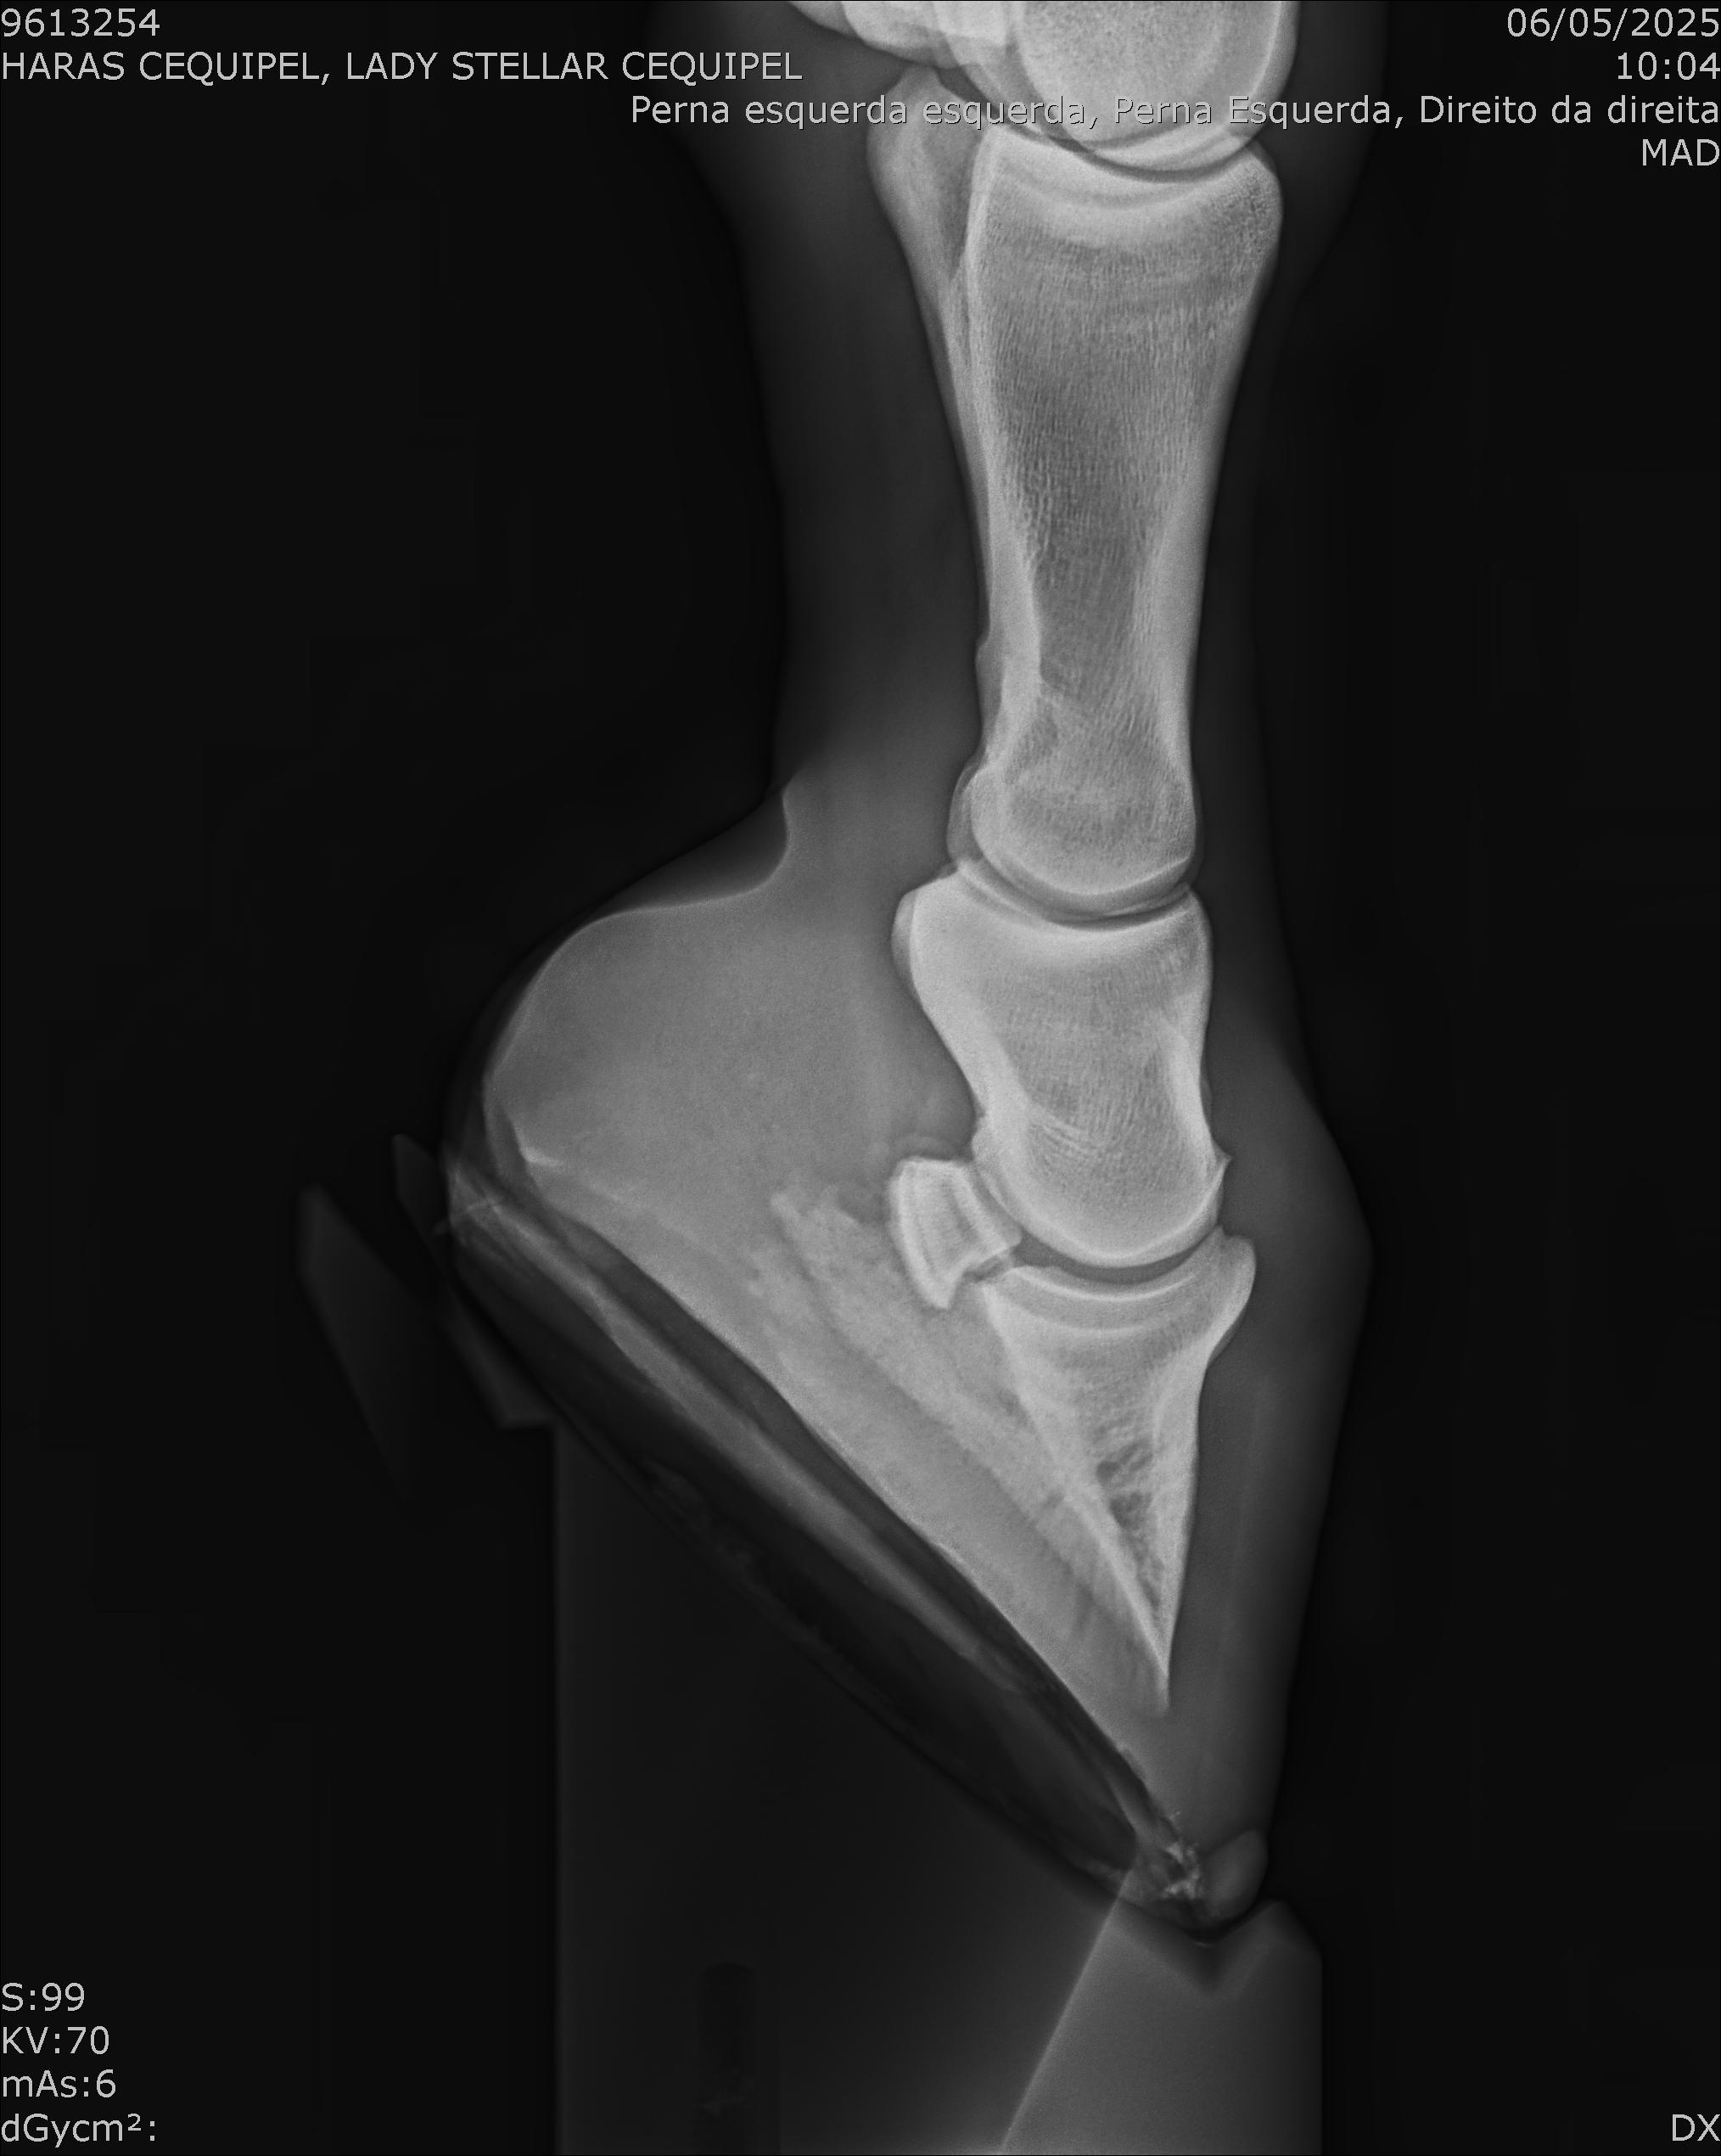

:: RAIOS-X DO LOTE